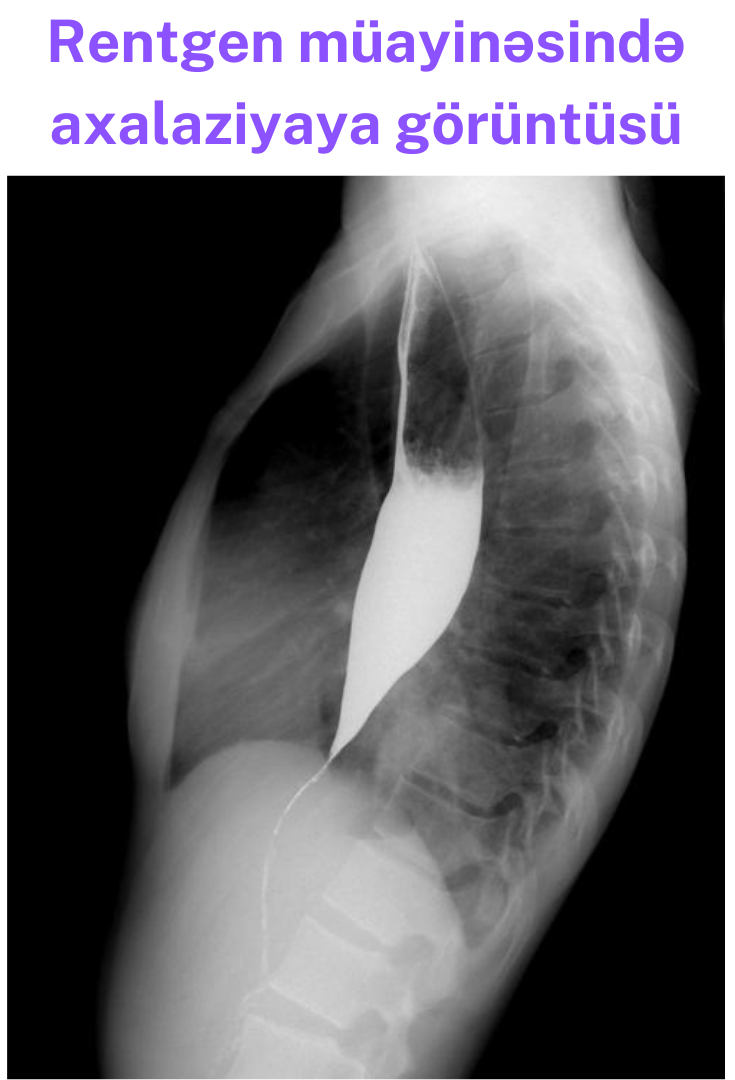

Qida borusunun rentgeni:

- Qida borusunun kardia hissəsinin qıfşəkilli daralması